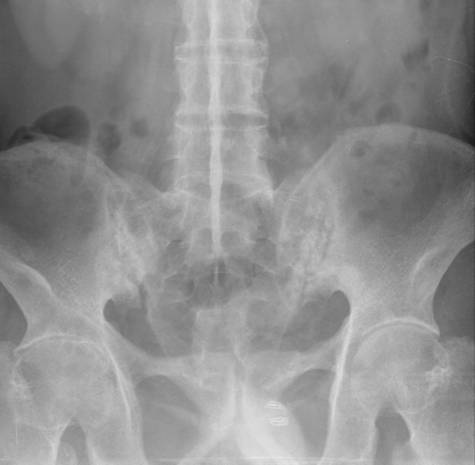

标题: CL0958:强直性脊柱炎

发生部位

骶髂关节---椎间小关节---椎旁韧带(棘上、棘间和黄韧带)

病理

骶髂关节、脊柱:骨炎---纤维组织增生---骨化、骨性强直。

四肢: 绒毛样增生---软骨破坏---纤维组织增生---骨化、骨性强直。

表现1、骨质硬化期:边缘骨质增生硬化;2、软骨破坏期:关节面边缘虫蚀状或锯齿状骨质破坏,边缘模糊,关节间隙增宽;3:骨性强直期:关节间隙消失,有骨小梁通过.